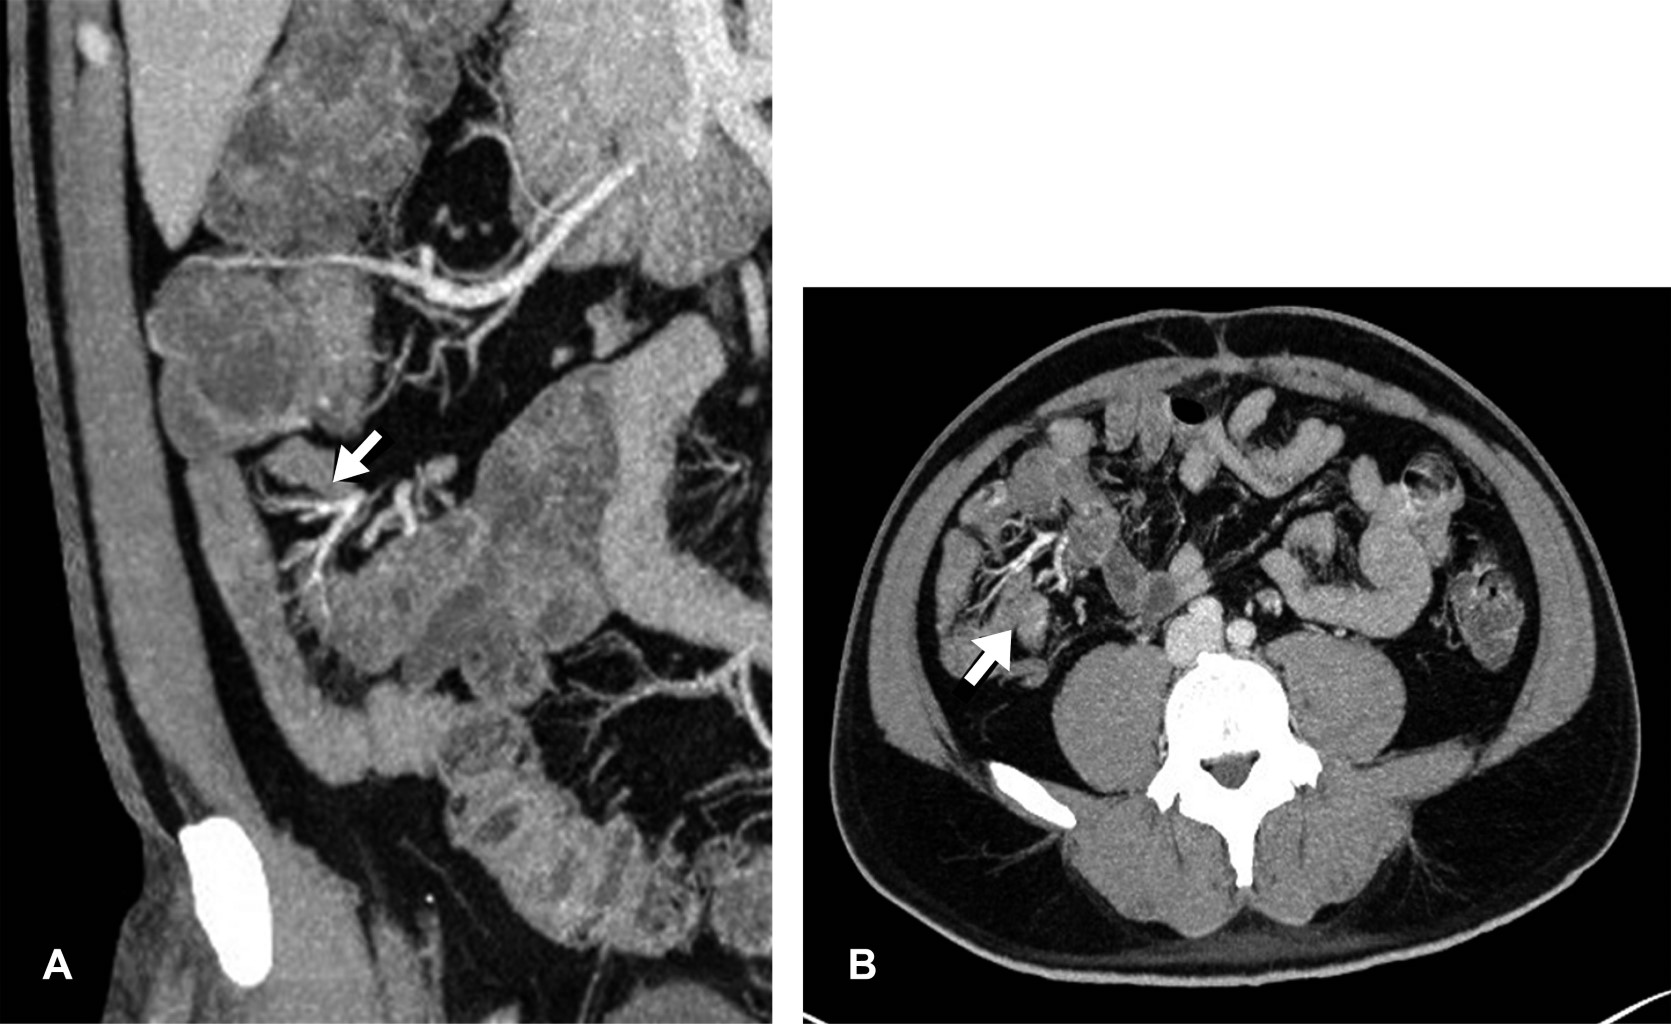

Introduction: polyarteritis nodosa (PAN) is a necrotizing vasculitis presenting as a multisystem disease. With aneurysmal formations in visceral arteries, especially in superior mesenteric artery branches. Case report: a 44-year-old male with abdominal pain in the epigastrium, nausea, and hematochezia, presenting petechiae on the trunk, abdomen, and pelvic limbs, predominantly with neutrophilic leukocytosis, negative immunological markers (ANCA). In abdominal angiotomography, sacculations are observed in superior ileal vessels. Conclusion: PAN is a rare multisystem vascular disease with a predilection for medium-caliber vessels. It is essential to identify radiological signs since a diagnostic delay leads to complications such as intestinal ischemia, aneurysmal ruptures, and others.

Figure 2